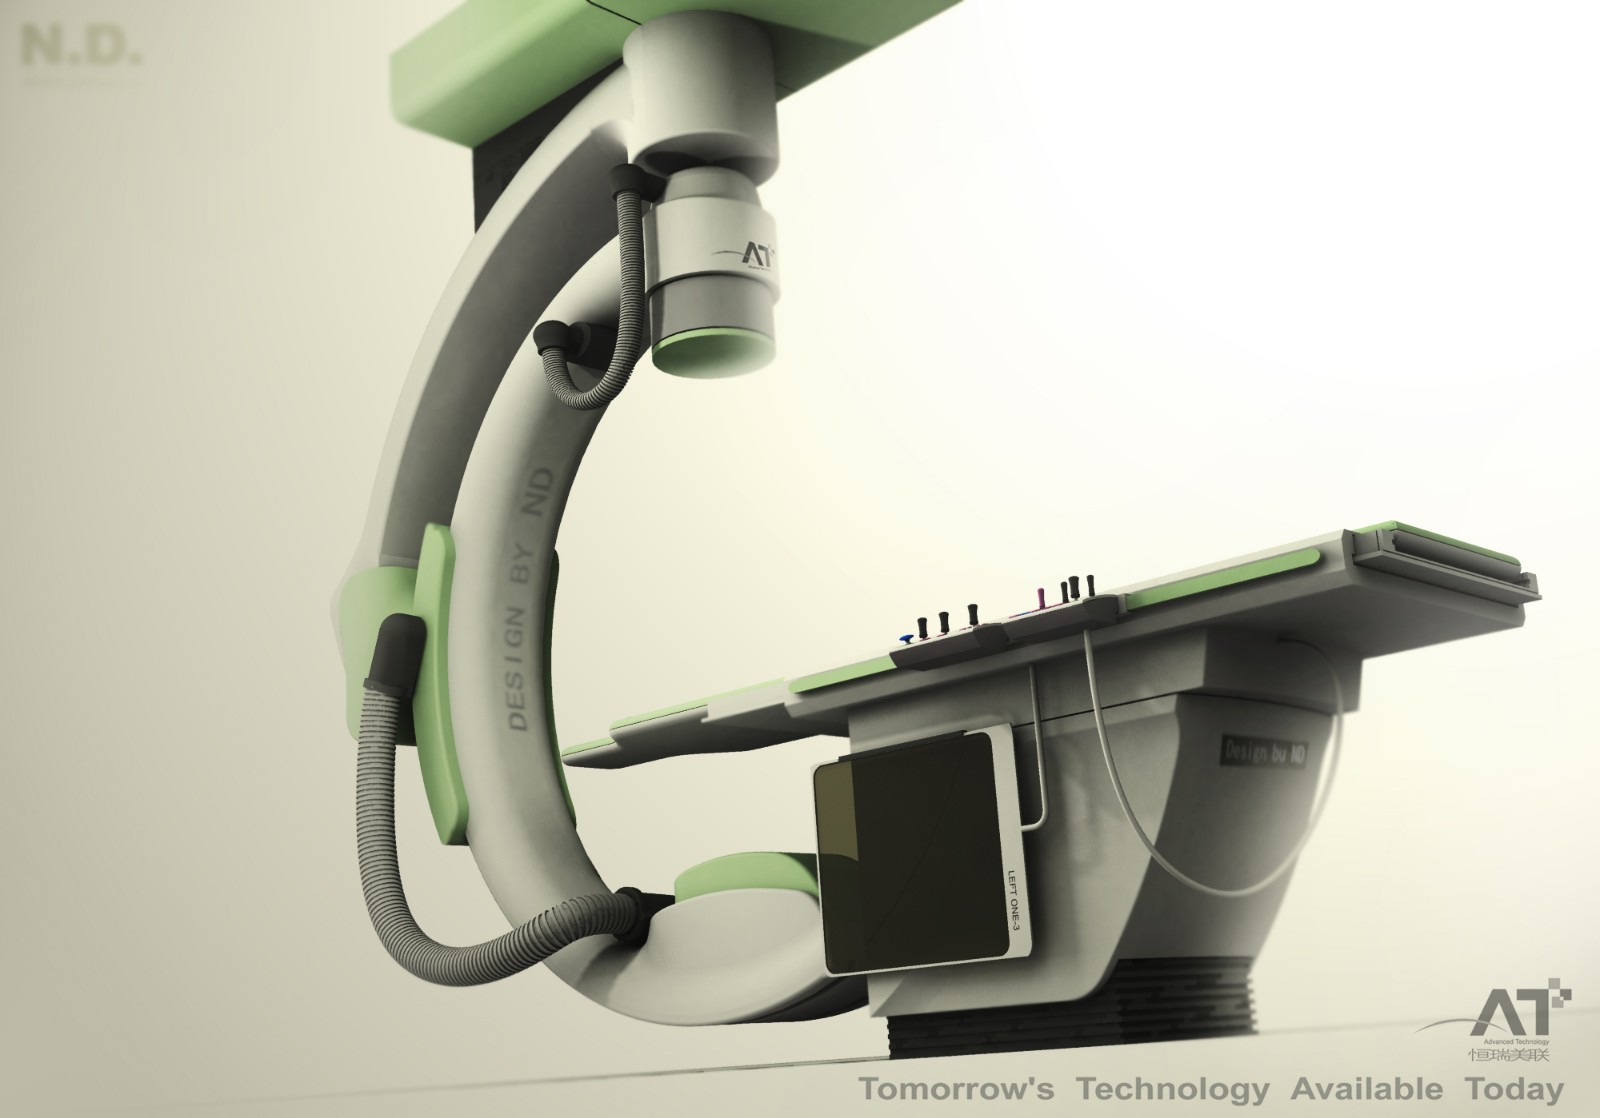

案例展示 ∥ 影像类设备 ∥ 系列放射类设备

2007年,设计团队花了近一年的时间来完成从机构到风格设计、工业设计、产品制造等全部工作。包括细节上的扶手、玻璃罩的设计,使外观更加富有设计感,但并非夸张复杂的设计风格,主要以功能为主,在满足产品功能的基础上,再进行了形式上的优化与风格的统一,我们经过与客户的紧密合作,出色地完成了客户的项目。

客户 | TCL医疗

项目 | 系列放射类设备

年份 | 2006